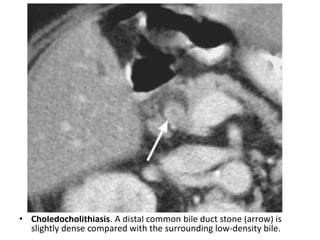

• Choledocholithiasis. A distal common bile duct stone (arrow) is

slightly dense compared with the surrounding low-density bile.

• Choledocholithiasis. Adistal common bile duct stone (arrow) is slightly dense compared with the surrounding low-density bile.